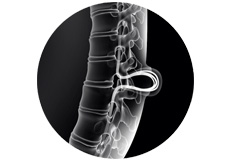

Lumbar Spine Anatomy

The spine also called the back bone, plays a vital role in stability, smooth movement and protection of the delicate spinal cord. It is made up of bony segments called vertebra with fibrous tissue called intervertebral discs between them.